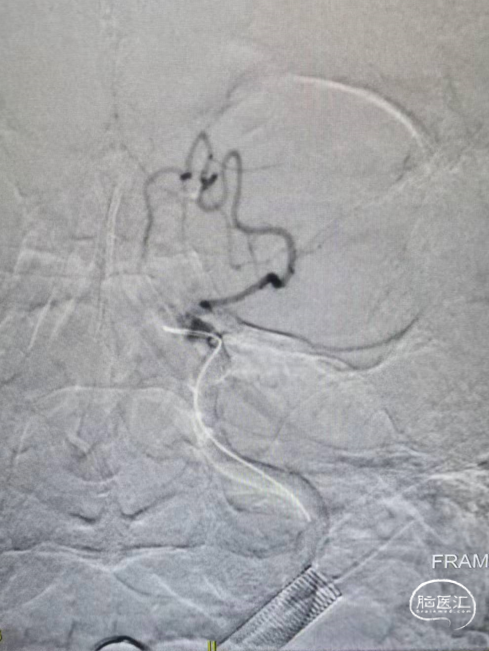

造影显示左侧的颈内动脉末端闭塞,中间导管造影显示大脑前和大脑中动脉显影,明确颈内末端闭塞。

中间导管到位之后送入RECO取栓支架 6*30cm、微导管,调整好微导管位置之后释放RECO取栓支架 6*30cm,支架展开之后血管血流通畅。

先负压抽吸,然后释放RECO取栓支架 6*30cm在负压下进行取栓操作。